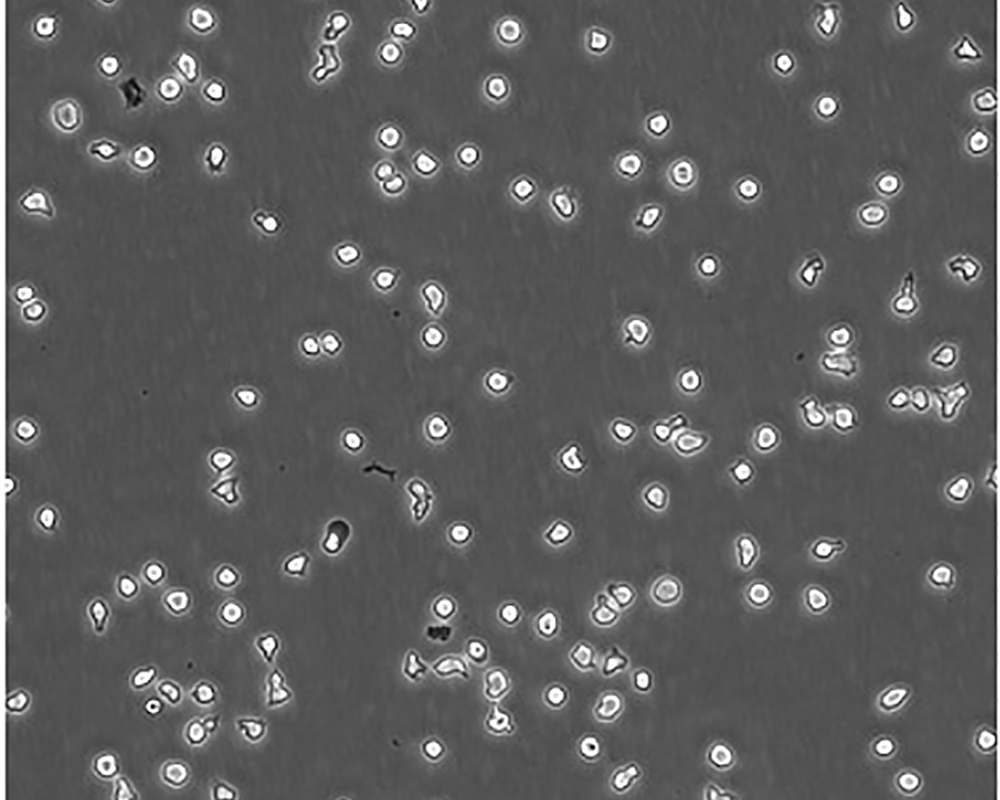

生長特性 suspension

形態特征 lymphoblast

傳代方法 Maintain cell density between 2×10^4 and 4×10^4 viable cells/mL.

細胞描述 一位套細胞淋巴瘤患者的巨細胞變種顯示白血病轉變,從其外周血單核細胞出發建立了MCL細胞株JeKo-1。 JeKo-1細胞EB病毒陰性,并表達一種B細胞表型的IgM。 細胞過表達cyclin D1, Bcl-2, c-Myc 及 Rb 蛋白。 Bcl-1/J(H)基因重排得到了PCR證實。 JeKo-1細胞在SCID小鼠中高成瘤。 [PubMed: 9753063]